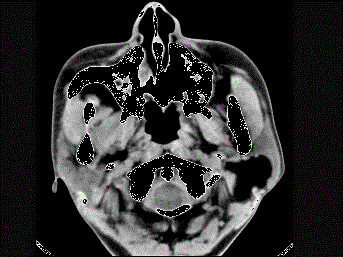

问题 女性50岁,左侧面部肿胀,CT检查如图,应考虑为 ( )

选项 A、左侧腮腺错构瘤 B、左侧腮腺炎 C、左侧腮腺囊肿 D、左侧腮腺脂肪瘤 E、左侧腮腺囊腺瘤

答案 D